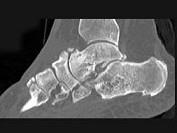

问题 男,56岁,踝关节肿胀,有糖尿病史,结合图像,最可能的诊断是?(?)

选项 A.创伤性关节炎 B.退行性关节病 C.痛风 D.类风湿关节炎 E.神经性关节病

答案 E